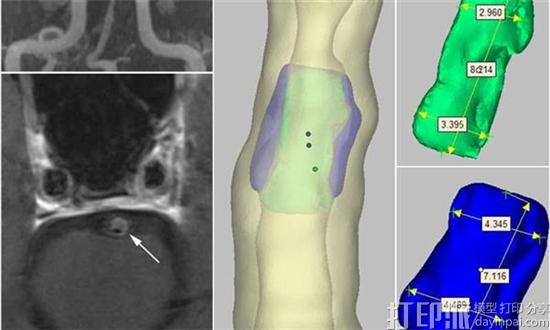

MUSC中风部主任Tanya N. Turan M.D.在“神经外科手术杂志”上发表了题为“开发高分辨率MRI颅内动脉粥样硬化成像体模”的文章。该文章阐述了她的团队与马萨诸塞大学的生物工程师合作开展工作。他们从MUSC的ICAD的单个患者中获取3D成像数据,并将其用于3D打印颅内动脉的“幻影”。他们创建的模型是高度准确的,模拟狭窄的容器和其斑块成分,包括纤维帽和脂质核心。

在Turan的文章中,基于从8个不同的高分辨率MRI扫描机构获得的数据,证明了使用该幻像进行全球标准化的可行性。其中6个在美国,两个位于中国,其中与中国分享数据至关重要。Turan正在与中国的北京协和医学院的Weihai Xu博士合作,收集有关参与机构间可靠性评估的更多数据。这是影响全球合作研究可能性的另一个关键因素。